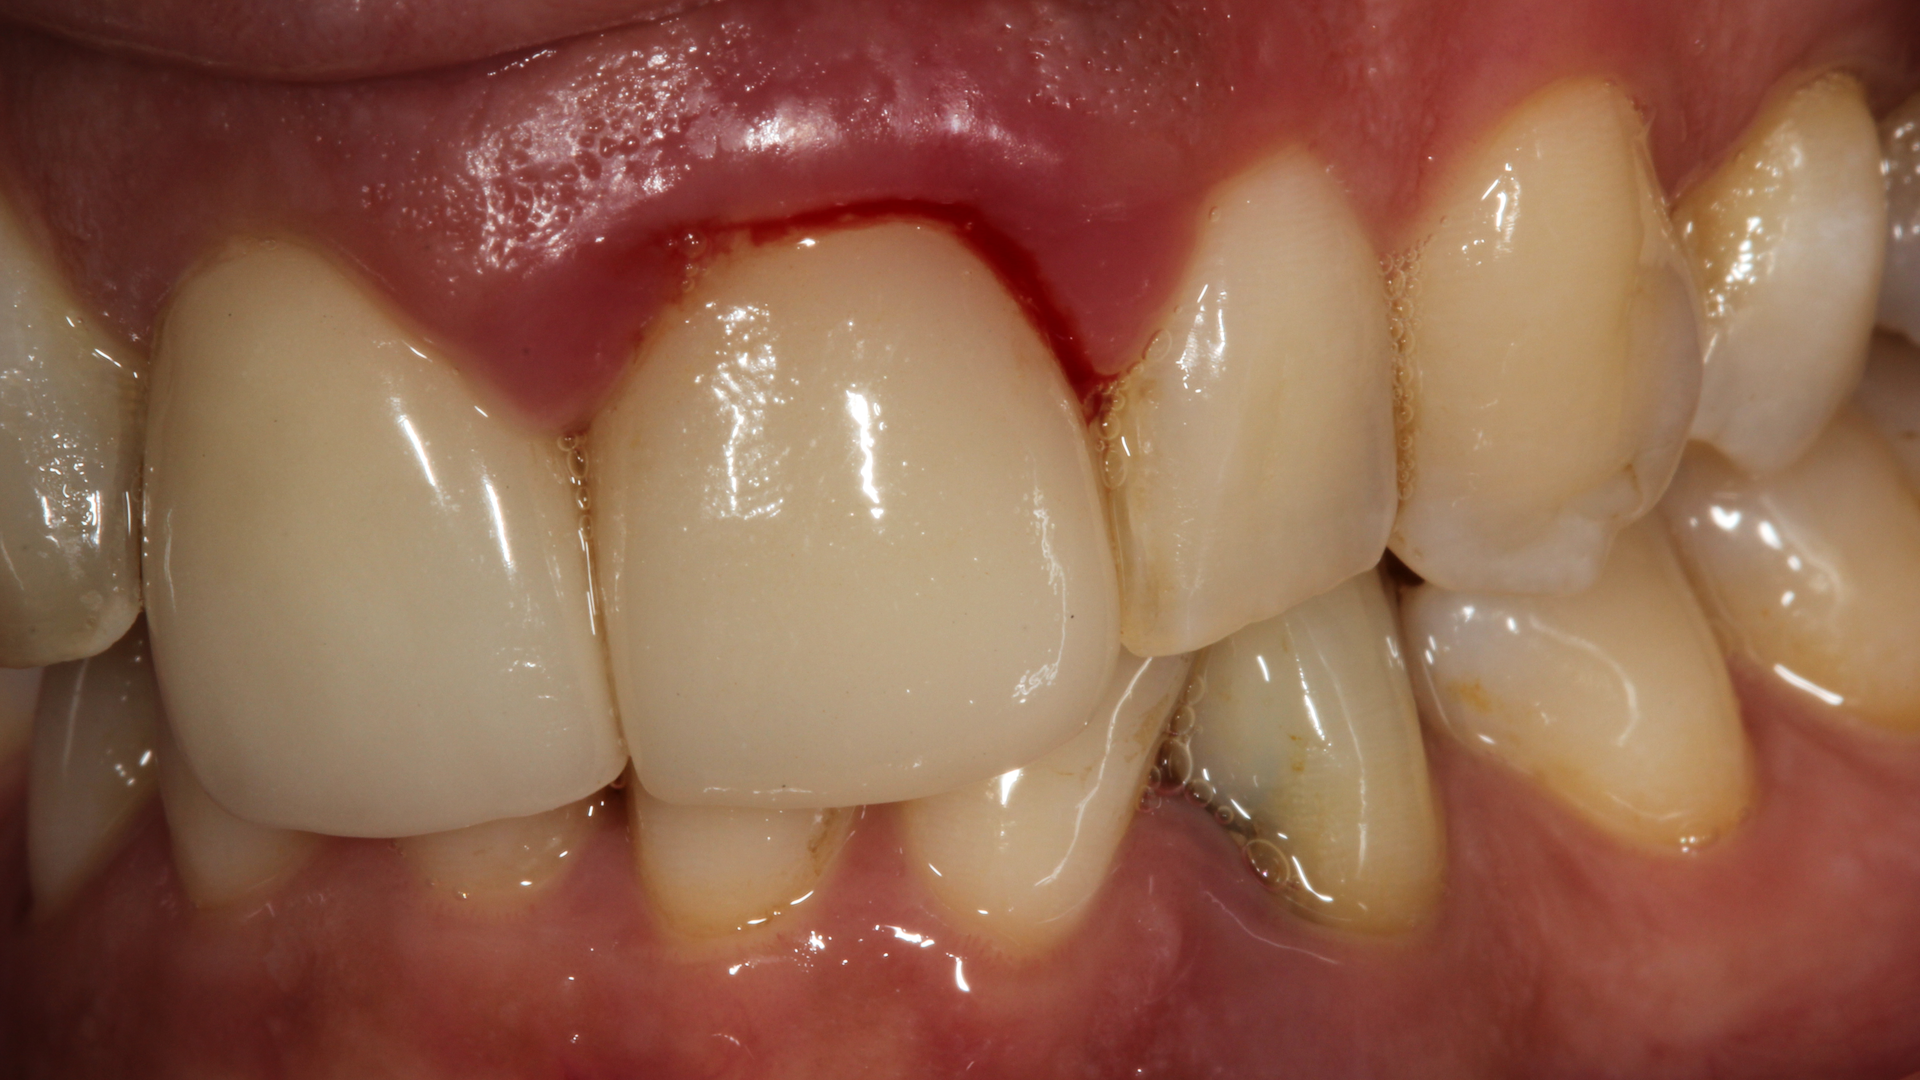

There are a multitude of reasons why patients may not respond properly to periodontal therapy or why their gums still bleed after a dental cleaning (figure 1).1 Of tantamount importance is to discern why previous therapy has not worked prior to reinitiating treatment or simply “giving the patient another cleaning.”

Studies have shown that multiple episodes of scaling and root planing (a deep cleaning) are no more effective than administering a single episode of scaling and root planing performed properly.1 The purpose of this article is to briefly discuss the top five reasons gingival inflammation persists after a dental cleaning.